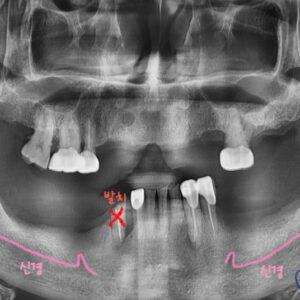

윗 어금니들이 다 빠지거나 부러진 환자분 께서 내원하셨습니다.

임플란트를 해야하는데 뼈가 없어서 안된다고 들으셨다고 오셨어요.ㅠㅠ

사진을 보시면 치아가 부러져서

작은 어금니는 뿌리만 남아있고

큰 어금니는 이미 상실되어있습니다..

구내 엑스레이 사진을 보면 양쪽 위 어금니들이

빠진지가 오래되어 상악동 함기화가 되어

임플란트 식립할 뼈가 부족합니다.

X 표시가 되어있는 치아는 발치하고

왼쪽은 치아 3개, 오른쪽은 치아 4개를 만들기로 계획을 세웁니다.